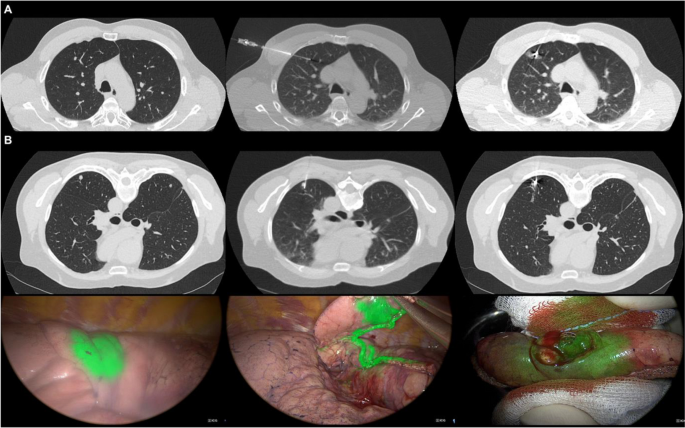

One of our latest articles published focuses on CT-guided percutaneous marking of lung nodules using patent blue V and indocyanine green

link.springer.com/article/10.100…